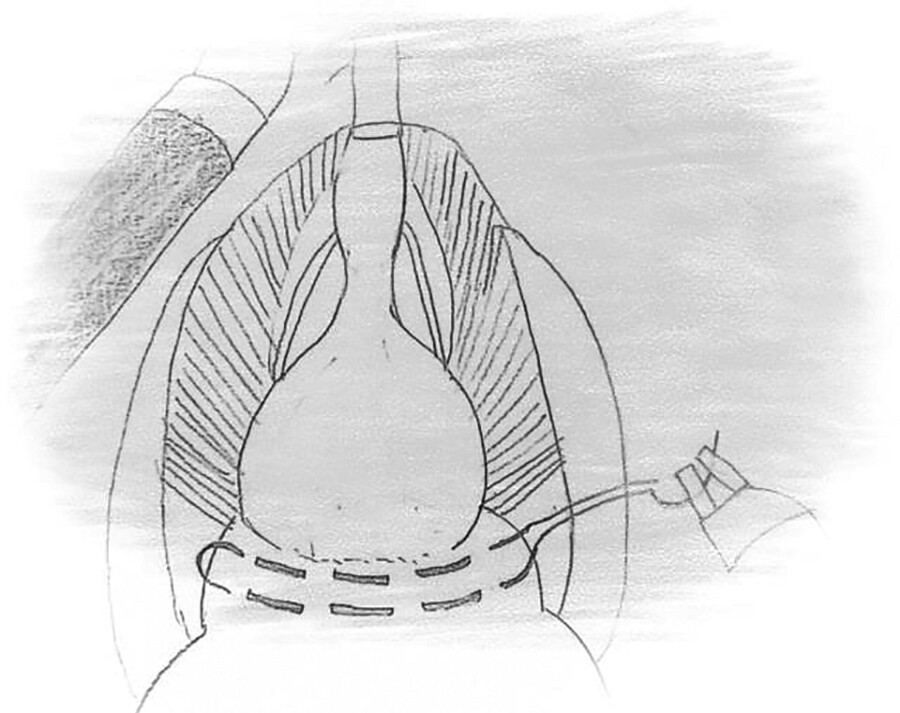

Modified Urethral Anastomosis Technique in Patients Undergoing Robotic Radical Prostatectomy: Tube-Shaped Bladder Neck

Authors: Mutlu Ateş, Yasin Aktaş, Kayhan Yilmaz, Mahmut Taha Ölçücü, Şahin Kiliç, and Murat Şambel

View Video